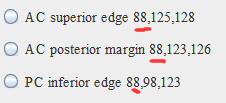

找到AC superior edge,点击set

找到AC posterior edge,点击set

(4)第二个目标是标记PC inferior edge

一般PC和AC的Y轴坐标相同,即第一个坐标